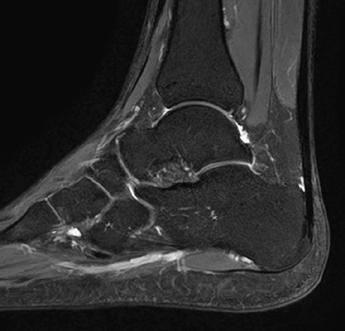

AiCE - High resolution imaging with short scan times

Ankle

16ch Flex SPEEDER, WFS (Water Fat Separation), AiCE, Res: 0.3 x 0.3 x 3 mm,

Scan time: 3:13 min.